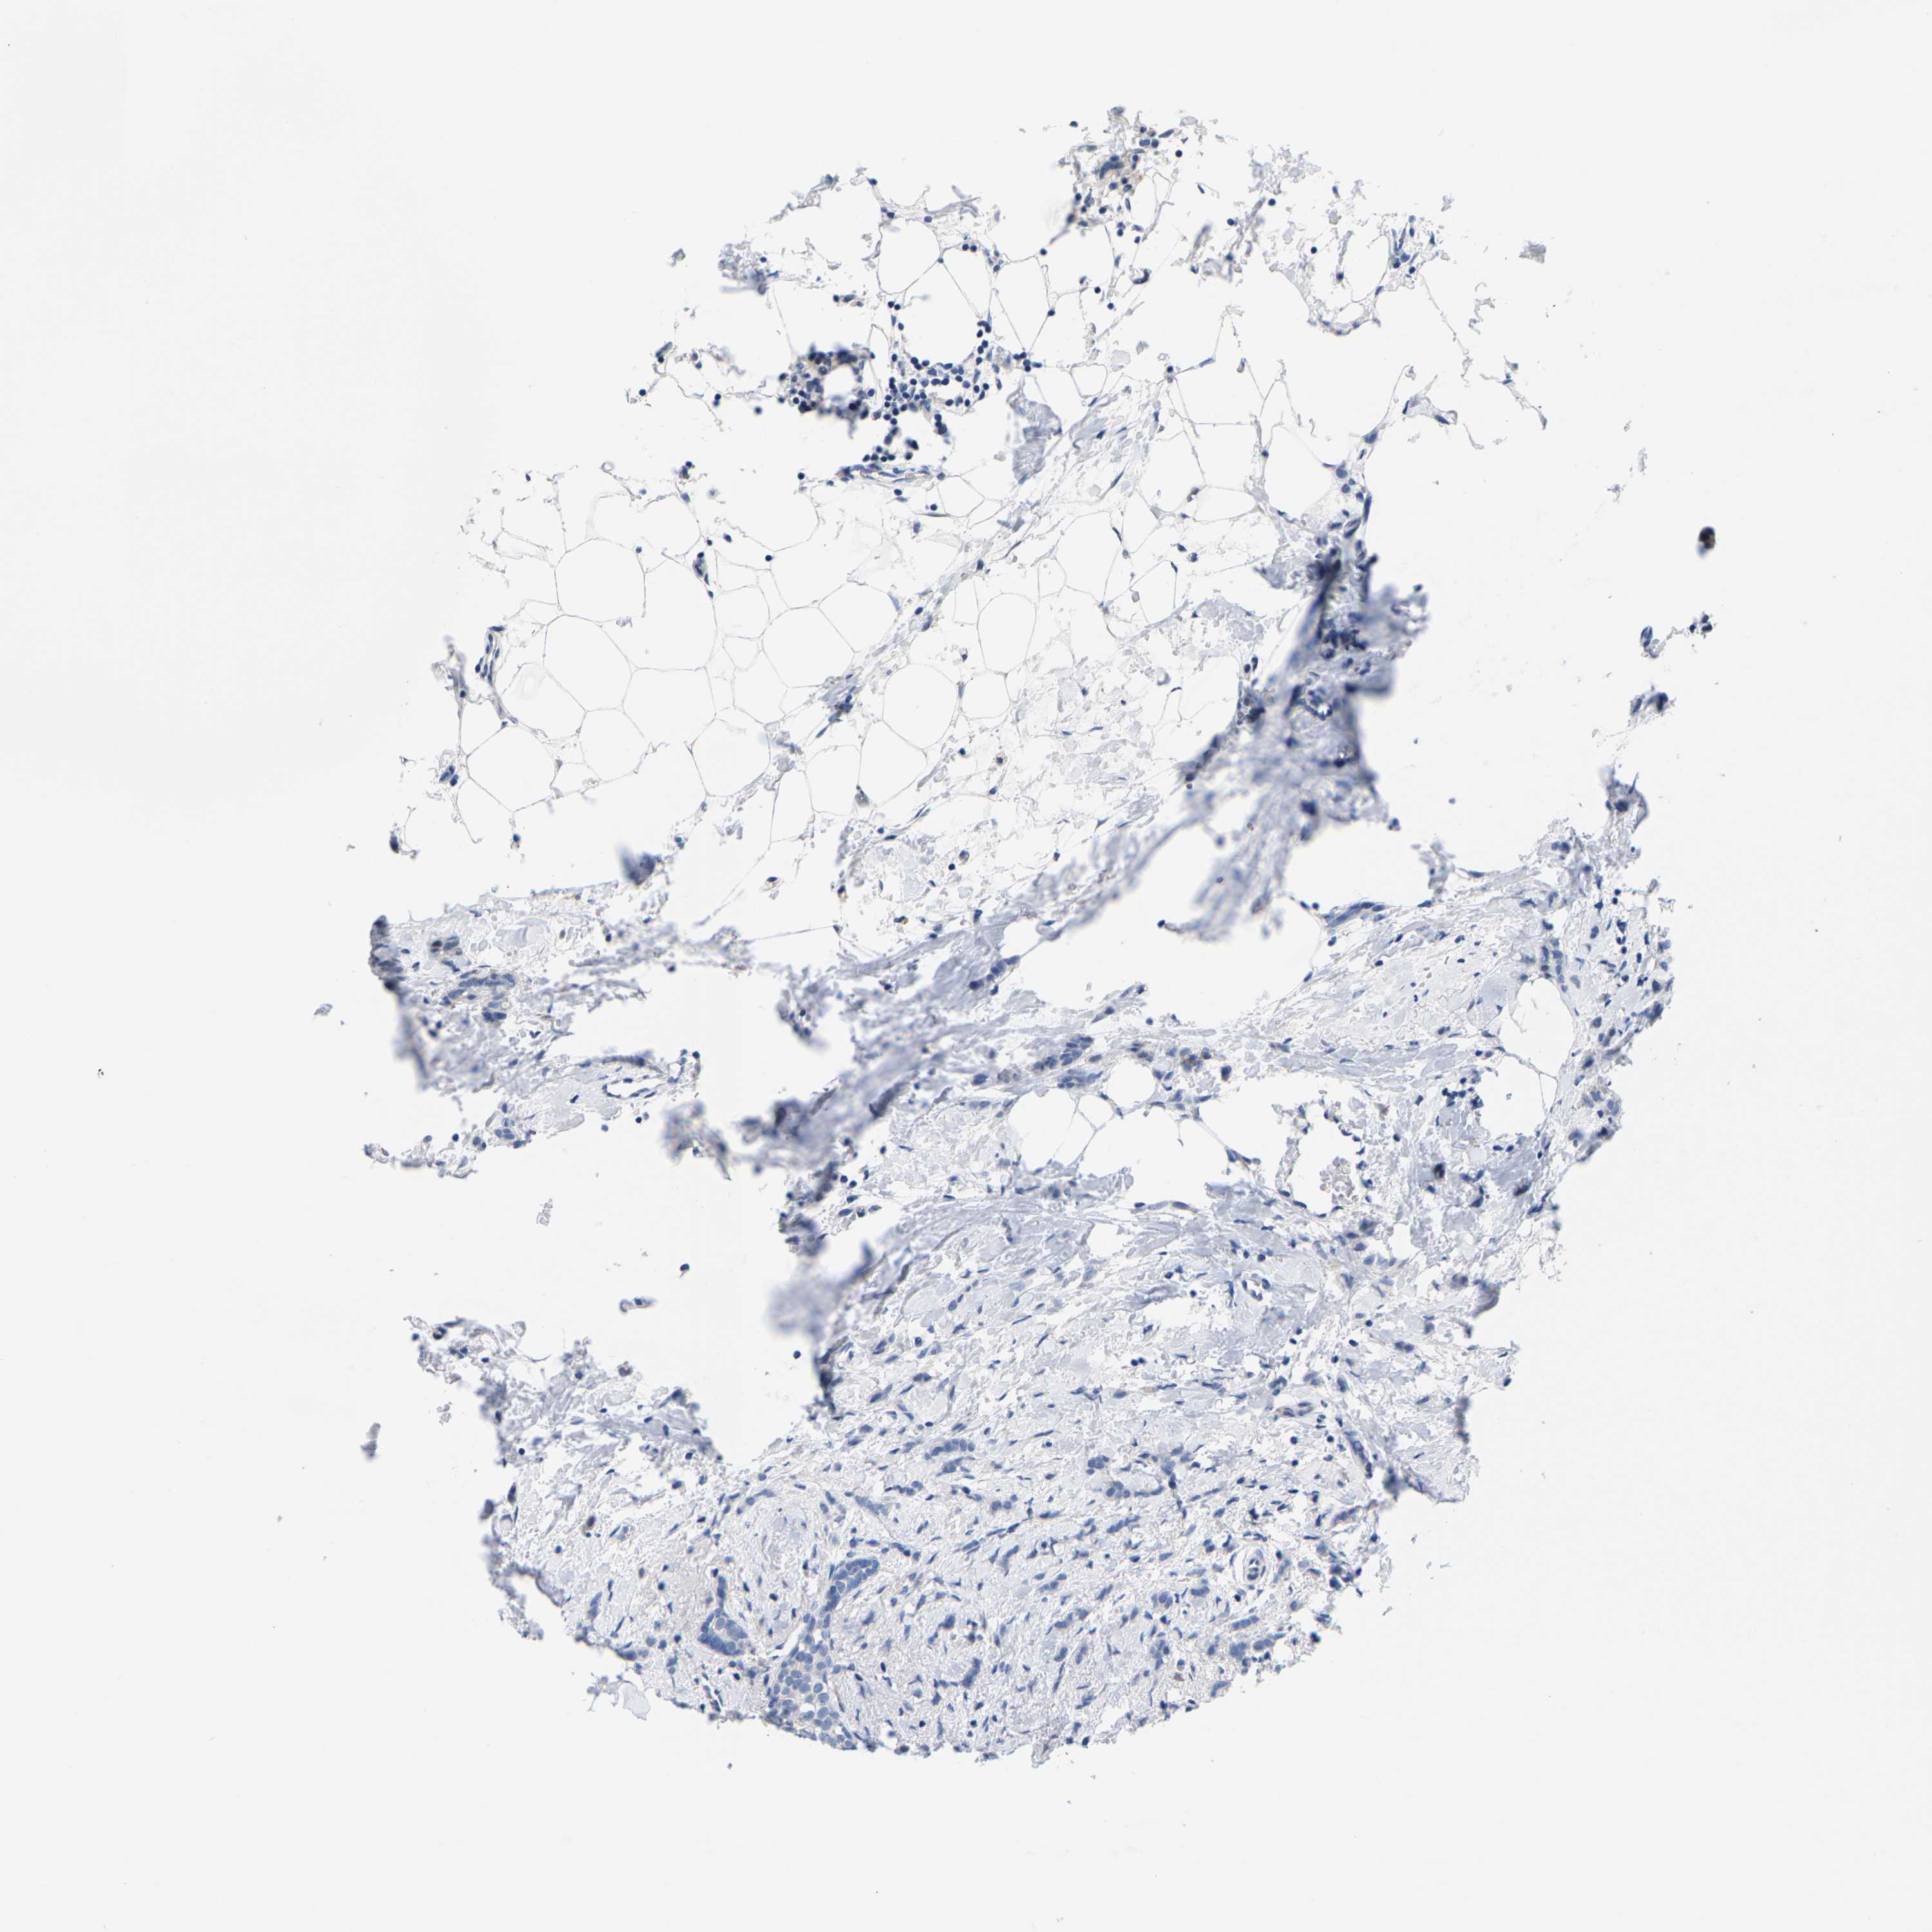

Breast cancer

Human cancer